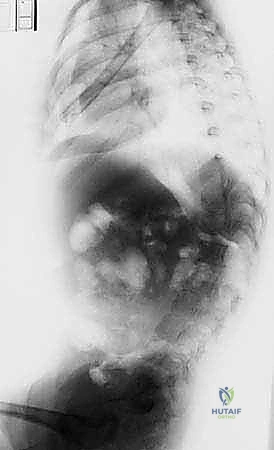

- الأشعة السينية (X-rays) البانورامية: يتم أخذ صور للعمود الفقري بالكامل من الأمام والخلف والجانب (أثناء وقوف الطفل أو جلوسه إذا كان لا يستطيع الوقوف). يتم من خلالها قياس "زاوية كوب" (Cobb Angle) لتحديد شدة الانحناء.